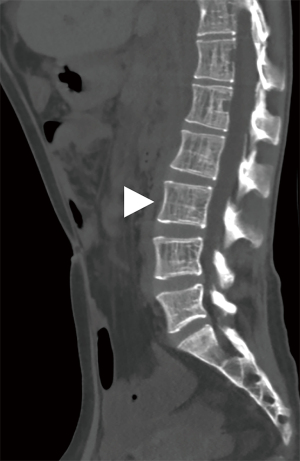

The involvement locations and incidence of bone lesions in 39 cases are detailed in Table 2. According to the morphology of bone lesions, these were divided into the following four types: (I) cystic changes (n=30; Figure 2), which showed single or multiple round-like cystic hypodense shadows in bone. The lesions had clear borders with or without sclerotic margins, and the maximum diameter was less than 5 cm. Marginal sclerotic margins (n=28), with one case showing iodized oil deposits within the lesion. (II) canal-like or honeycomb-like changes (n=34; Figure 3), which showed a tortuous, tubular distribution of hypointense shadow with clear margins and continuous at multiple levels above and below. The bone cortex was smooth or irregularly fractured in a worm-like pattern, while lesions were seen in 20 cases with iodized oil deposits. (III) Osteoporosis-like changes (n=16 cases; Figure 4), which showed a diffuse decrease in bone density and thinning of bone trabeculae. No lipiodol deposition was seen in any of the 16 cases in this group. (IV) Osteosclerosis-like changes (n=8; Figure 5), with two cases showing smooth thickening of the bone cortex, three cases showing increased density of osteophytes in the medullary cavity, three cases showing mixed presence, and five cases showing narrowing of the medullary cavity. Iodized oil deposition was not observed in any case.